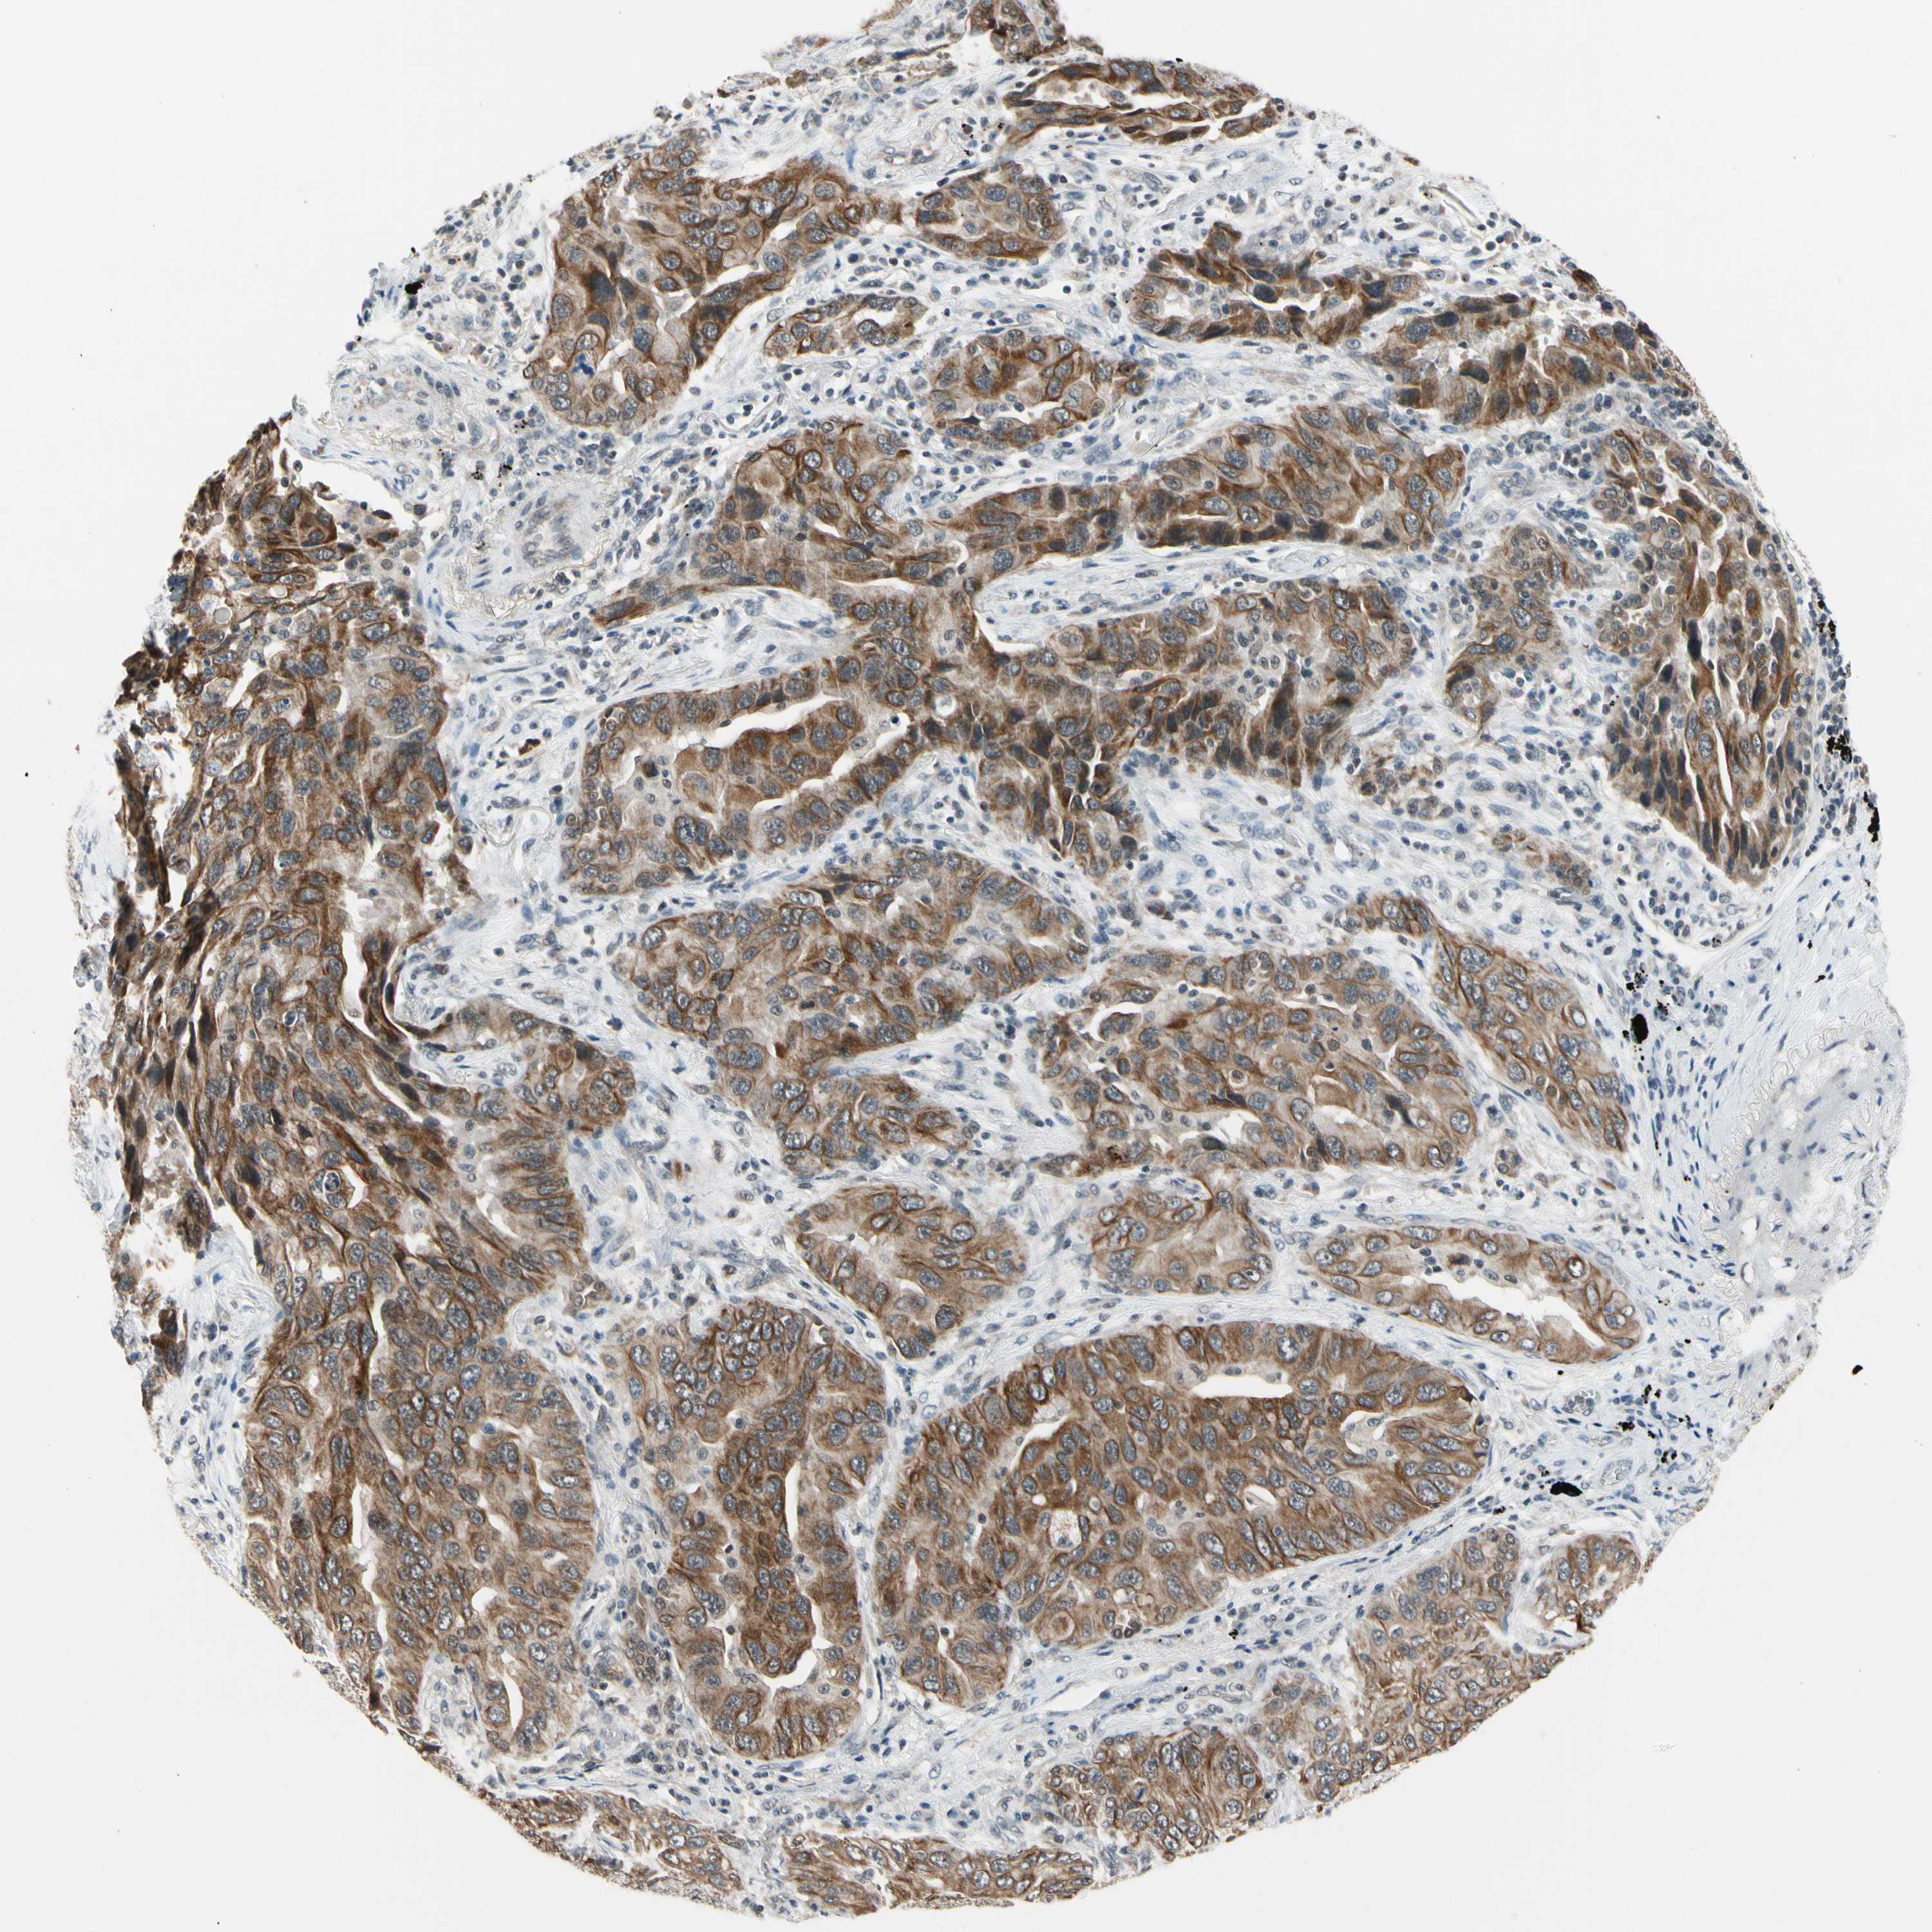

TAF12